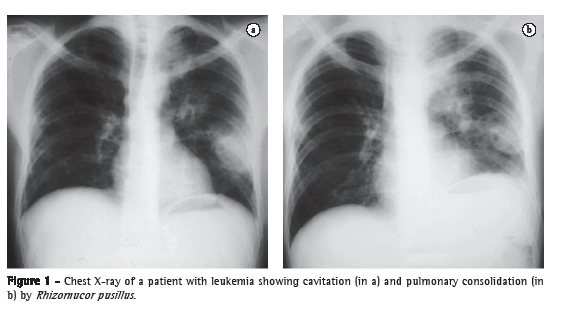

Tomographic findings demonstrate wedge-shaped infiltrates or consolidations and masses.(3) Consolidations are present in approximately 66% of cases, whereas cavitations are present in 40% (Figure 1).(1,3) The halo sign with ground-glass opacity, surrounding the pulmonary nodule, represents hemorrhage and edema, and can develop before and after the neutropenic phase.(1,17) Pleural effusion and multiple nodular pulmonary infiltrates (more than 10) are independent predictors of zygomycosis.(13,18) Chest HRCT can be sensitive in 26% of unsuspected lesions.(15,19)